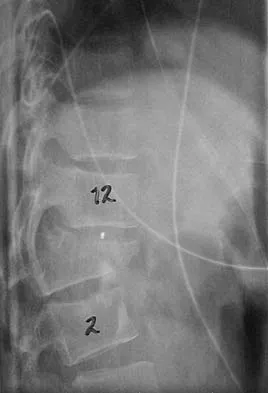

Question 25

A 25-year-old man has chronic back pain that has been slowly worsening. He has no constitutional symptoms, and he denies any previous medical problems. Examination shows a tall lean build with no objective neurologic findings or skin lesions. Figure 32 shows a T2-weighted sagittal MRI scan. What is the most likely diagnosis?

Explanation